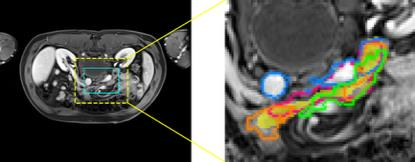

Accurate magnetic resonance imaging (MRI) segmentation is crucial for clinical decision-making, but remains labor-intensive when performed manually. Convolutional neural network (CNN)-based methods can be accurate and efficient, but often generalize poorly to MRI's variable contrast, intensity inhomogeneity, and protocols. Although the transformer-based Segment Anything Model (SAM) has demonstrated remarkable generalizability in natural images, existing adaptations often treat MRI as another imaging modality, overlooking these modality-specific challenges. We present SAMRI, an MRI-specialized SAM trained and validated on 1.1 million labeled MR slices spanning whole-body organs and pathologies. We demonstrate that SAM can be effectively adapted to MRI by simply fine-tuning its mask decoder using a two-stage strategy, reducing training time by 94% and trainable parameters by 96% versus full-model retraining. Across diverse MRI segmentation tasks, SAMRI achieves a mean Dice of 0.87, delivering state-of-the-art accuracy across anatomical regions and robust generalization on unseen structures, particularly small and clinically important structures.